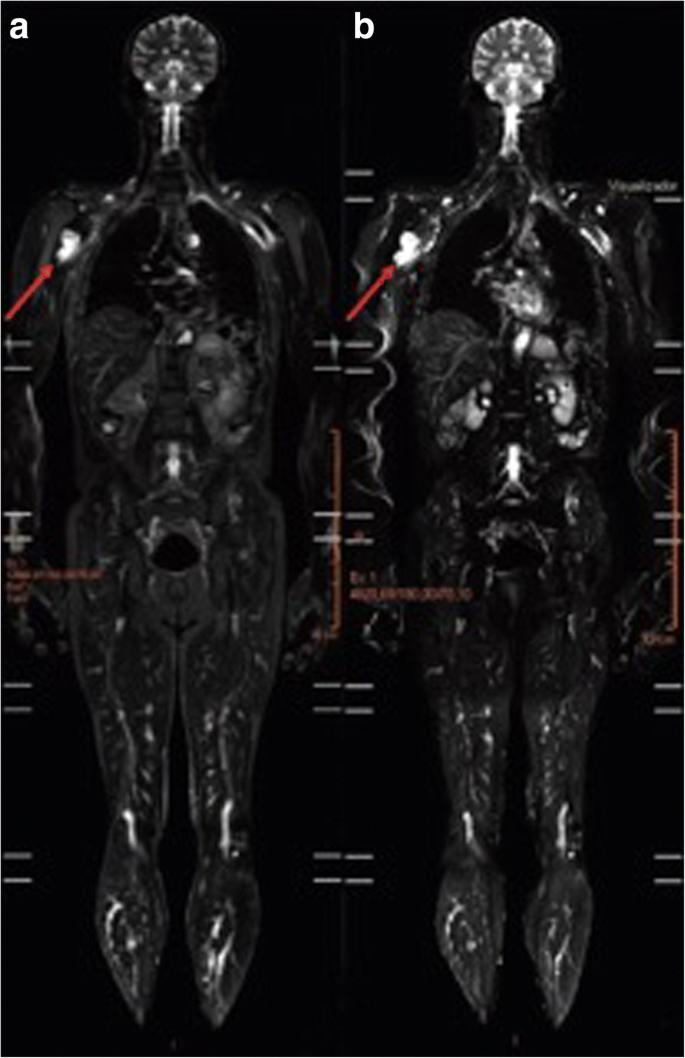

A Meta-analysis These data suggest clinical utility of baseline WBMRI in TP53 germline mutation carriers and may form an integral part of baseline clinical risk management in this high-risk population. Li-Fraumeni syndrome LFS is an inherited familial predisposition to a wide range of certain often rare cancers. The whole exam takes approximately 2 hours though a separate dedicated breast MRI should be performed in women.

The chief advantage of MRI in this setting is its lack of ionizing radiation. This cohort study of patients with Li-Fraumeni syndrome assesses the diagnostic yield and false-positive rate of an annual surveillance program including whole-body magnetic resonance imaging in patients identified as carriers of TP53 gene mutations. Context Individuals with Li-Fraumeni syndrome LFS have an inherited cancer predisposition to a diverse array of malignancies beginning early in life.

Li-Fraumeni syndrome LFS is an inherited familial predisposition to a wide range of certain often rare cancers. Li Fraumeni Syndrome MRI can be used to evaluate the whole body to detect tumors in Li-Fraumeni syndrome. Adults 18 years with a diagnosis of Li-Fraumeni Syndrome LFS may be screened for malignancy with a Whole Body MRI CPT 76498 on an annual basis. The chief advantage of MRI in this setting is its lack of ionizing radiation. 39 rows Approximately 80 of families with the features of Li-Fraumeni Syndrome. The resulting p53 protein produced by the gene is damaged or otherwise rendered malfunctioning and is unable to help prevent malignant tumors from developing. Li-Fraumeni syndrome also known as SBLA syndrome is due to germline mutations in the gene TP53 p53 an important regulator of apoptosis and the cell cycle ie. Survivors of one cancer have a markedly elevated risk of additional primary tumors. This is due to a change mutation in a tumor suppressor gene known as TP53.